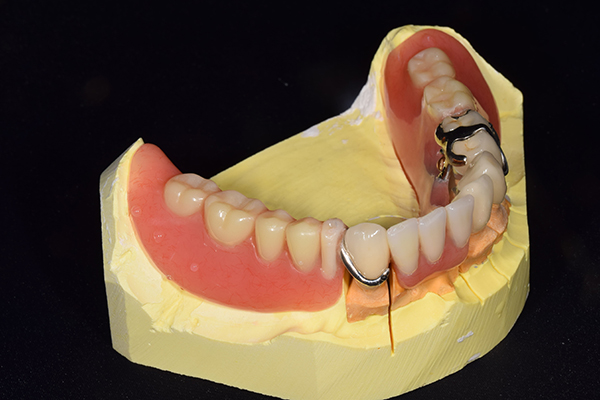

金属を使用して、薄く違和感が少ない入れ歯が完成しました。 また、見た目にも気を使い、バネが見えにくい様な構造にしました。

義歯は下顎で、しっかり噛めること、違和感の少ないものという希望があったため、なるべく入れ歯を薄く作成するために金属をしようした義歯とした。

また、見た目もあまり義歯が目立たない様に、バネの部分を見えにくいように作成した。

入れ歯は極力薄くするために金属を使用しました。しっかり噛める様にするため、ノンメタルクラスプデンチャーにはしませんでした。

上の入れ歯(表)

上の入れ歯(裏)

下の入れ歯